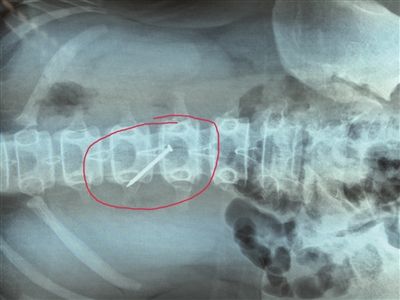

原標題:13歲女孩,為何吞下4厘米長鐵釘?

長約4厘米的鐵釘被取出時,已刺穿13歲女生的胃壁。 朱鼎兆 攝

一根長近4厘米的鐵釘在胃里會怎么樣?29日下午4時許,在淮安市婦幼保健院,該院小兒科醫生就從宿遷泗陽一名13歲女生小軒(化名)的胃里成功取出一根長約4厘米的鐵釘,而此時,這根鐵釘已經刺破了小軒的胃壁。